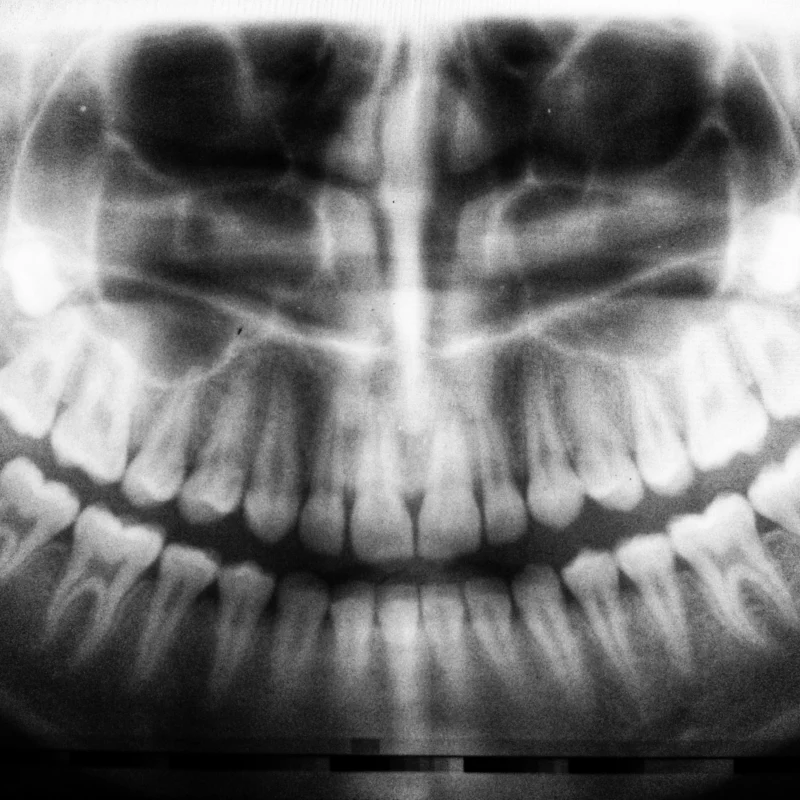

Diş Dolgusu: Ağız Sağlığının Koruyucusu

Diş dolgusu, diş çürüğünün ilerlemesini durduran ve dişin doğal yapısını koruyan etkili bir tedavi yöntemidir. Dişteki çürük bölge özel aletlerle temizlenir ve sonrasında uygun bir dolgu maddesiyle doldurulur. Bu işlem sayesinde hem ağrı ortadan kalkar hem de dişin işlevselliği geri kazanılır.

Diş Dolgusu Türleri Nelerdir?

Günümüzde farklı dolgu materyalleri mevcuttur ve her biri farklı ihtiyaçlara cevap verir:

- Kompozit Dolgu (Beyaz Dolgu): Estetik açıdan doğal diş rengine yakın olduğu için sıkça tercih edilir.

- Amalgam Dolgu (Gümüş Dolgu): Özellikle azı dişlerinde uzun ömürlü bir çözüm sunar.

- Cam İyonomer Dolgu: Özellikle çocuklarda ve geçici dişlerde tercih edilir.

- Seramik Dolgu: Porselen içeriklidir, dayanıklılığı ve estetik görünümü ile öne çıkar.